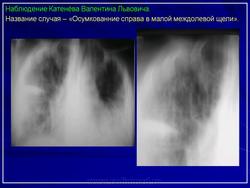

Иллюстрации 1, 2. Теневая картина осумкованного выпота в малой междолевой щели.